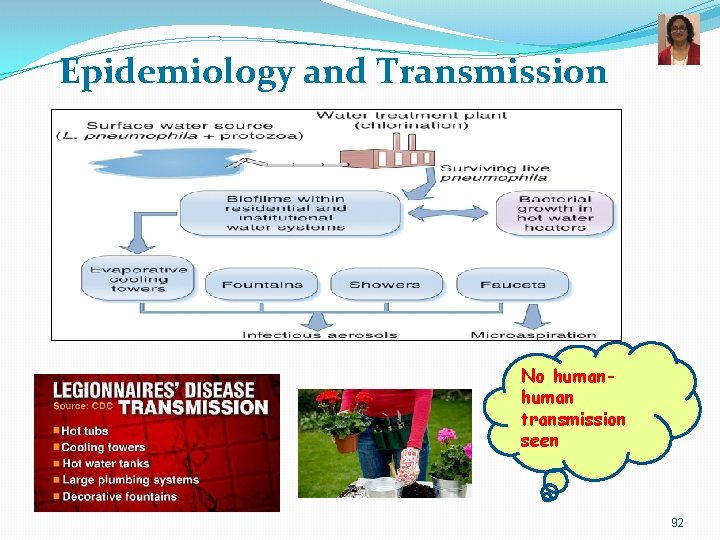

Epidemiology and Trends Outbreaks are commonly associated with buildings or structures that have complex water systems, like hotels and resorts, long-term care facilities, hospitals, and cruise ships. About one in 10 people who gets sick from Legionnaires’ disease will die Can be transmitted in the hospital set up Keeping Legionella out of water systems in buildings is key to preventing infection. 90

Epidemiology and Transmission No human transmission seen 92